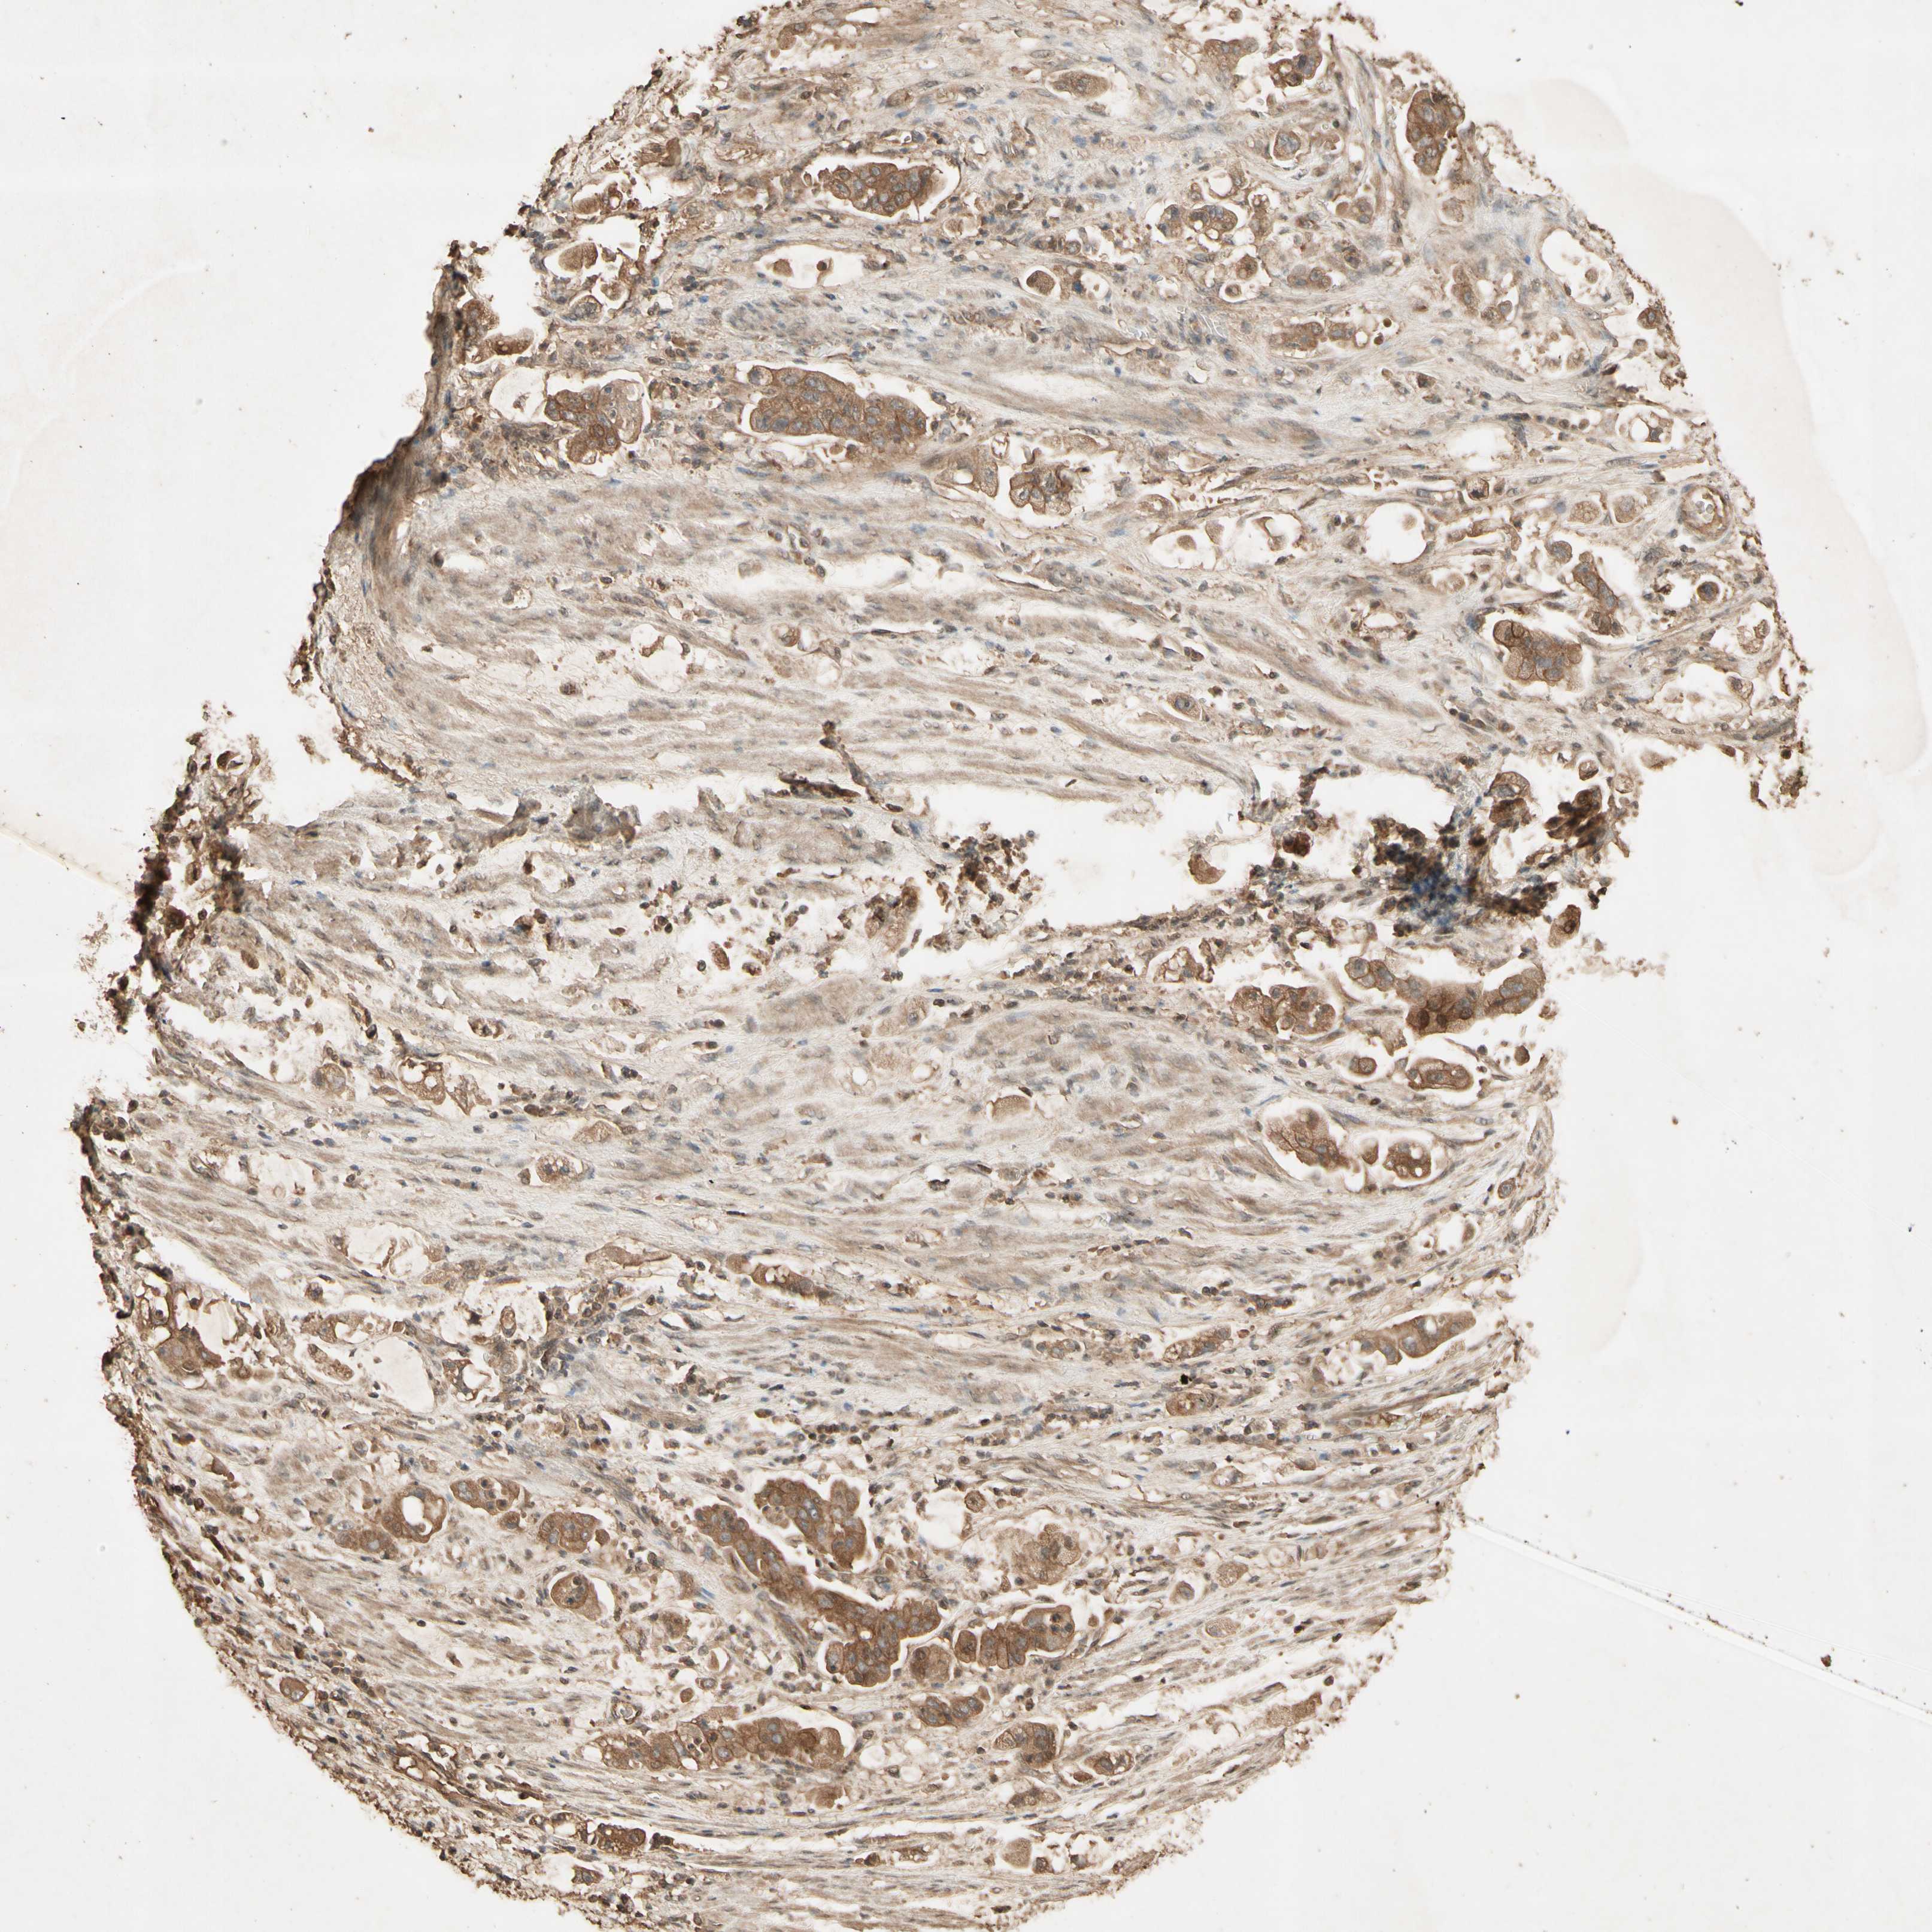

STOMACH CANCER - Protein expressioni

A mouse-over function shows sample information and annotation data. Click on an image to view it in a full screen mode. Samples can be filtered based on level of antibody staining by selecting one or several of the following categories: high, medium, low and not detected. The assay and annotation is described here.

Note that samples used for immunohistochemistry by the Human Protein Atlas do not correspond to samples in the TCGA dataset.

Antibody stainingi

Antibody staining in the annotated cell types in the current human tissue is reported as not detected, low, medium, or high, based on conventional immunohistochemistry profiling in selected tissues. This score is based on the combination of the staining intensity and fraction of stained cells.

Each image is clickable and will lead to virtual microscopy that enables deeper exploration of all samples and also displays staining intensity scores, fraction scores and subcellular localization as well as patient and tissue information for each sample.

Antibody HPA031162

Antibody CAB009119

Staining

High

Medium

Low

Not detected

Intensity

Strong

Moderate

Weak

Negative

Quantity

>75%

75%-25%

<25%

None

Location

Nuclear

Cytoplasmic/membranous

Cytoplasmic/membranous,nuclear

Adenocarcinoma, NOS

Adenocarcinoma, High grade